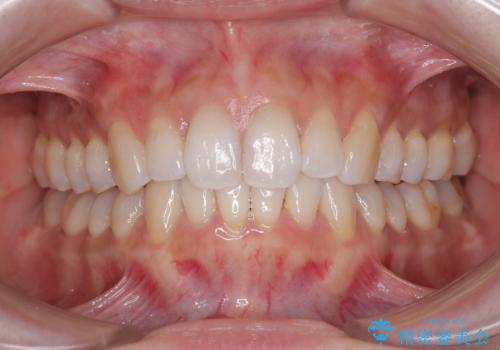

- 失活により変色した歯と不揃いな口元を気にして来院された患者様です。

口元をインビザラインにより歯列を整え、その後に失活している奥歯をオールセラミッククラウンにて補綴治療することとしました。

長時間のマウスピース装着と、患者様自身でのゴムかけに協力いただき、自然な口元に仕上げることができました。

気になっていた変色した歯もオールセラミッククラウンで本物の歯のようになり、患者様には大変満足していただきました。